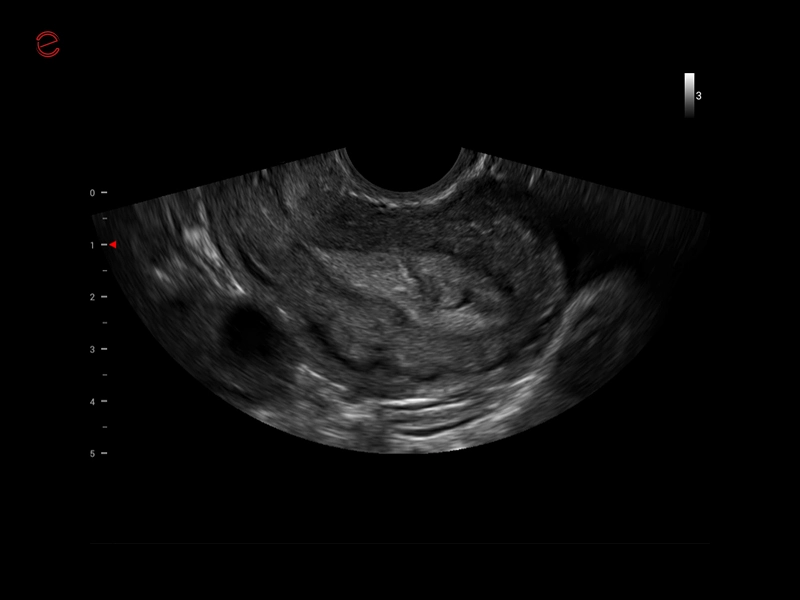

MyLab™X1 Go - WH Endometrium

MyLab™X1 Go - WH Endometrium